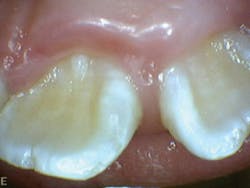

- Molar and cuspids right and left: Class I occlusion (see Figure 5)

- Slight crowding No. 22 and No. 26 (see Figure 6)

- Crossbite No. 10

- Midline 1 mm shift to left

Patient Q had tendency to have bruxism and clenching of teeth (see Figure 8). This was visible on occlusal/incisal surfaces of teeth K, L, M, R, S, T, B, C, H, and I (see Figure 7). She also exhibited evidence of mouth breathing. There was inflammation on the maxillary and mandibular anterior facial and lingual surfaces (see Figure 8).

Figure 5: Patient Q, occlusion

Figure 6: Patient Q, mandibular anterior crowding

Figure 7: Patient Q, side profile

Figure 8: Patient Q, mouth breathing and inflammation